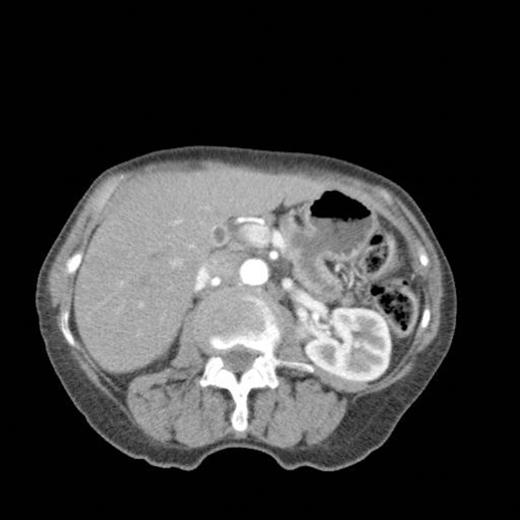

CT scan showing pancreatic duct dilatation to 15 mm with side branch dilatation in uncinate process and atrophic pancreas

CT scan done 2 years later revealed marked dilatation and tortuosity of the main pancreatic duct (12-13mm at the head) with atrophy of the body and tail (Fig1). Repeat scans done on an yearly basis over the next three years reported no progressive change. CT scan done 6 years after the original diagnosis revealed pancreatic duct dilatation to 15 mm with side branch dilatation in uncinate process and atrophic pancreas (Fig 2). A diagnosis of mucinous ductal ectasia or an intraductal papillary mucinous tumour was suggested. On clinical review, patient complained of epigastric discomfort, loose stools, anorexia and weight loss. Upper GI endoscopy and colonoscopy was normal. Faecal elastase was less than 100 confirming pancreatic insufficiency for which she was commenced on creon.